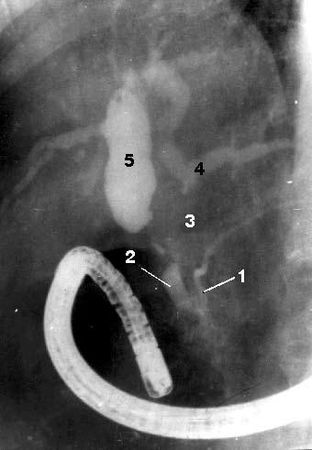

Рис. 106. Макропрепарат той же больной после ПДР. Рак головки ПЖ, прорастающий ДПК (3) и вызывающий резкий стеноз (2) выходного отдела желудка (1).

Диагноз основывается на изменениях, обнаруживаемых на панкреатограммах (стеноз или обструкция протока ПЖ), характер которых зависит от размеров опухоли, ее локализации и взаимоотношения с протоковой системой органа. Опухоль, исходящая из эпителия ГПП или располагающаяся в непосредственной близости от него, даже при небольших размерах быстро приводит к изменениям во всей системе протоков. При локализации рака на некотором расстоянии от ГПП изменения в первую очередь возникают в мелких протоках, тогда как в главном протоке их нет (рис. 108).

Рис. 108. Эндоскопическая ретроградная холангиопанкреатикография. Рак головки ПЖ, механическая желтуха.

Контрастированы терминальный отдел общего желчного протока (2) и главного панкреатического протока (1) в области головки и тела ПЖ. Общий печеночный проток (4) заполнен контрастом только в месте слияния долевых печеночных протоков, имеется продленный его стеноз в месте опухоли (3). Желчные протоки выше препятствия расширены, увеличение желчного пузыря (5)